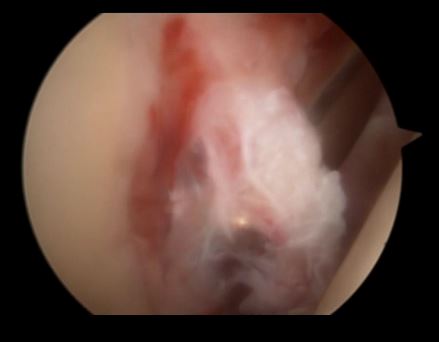

炎性肩关节——充血——滑膜炎

关节镜下可以彻底的清理关节内炎性滑膜组织及黏连带(盂肱关节及肩峰下关节)

黏连带